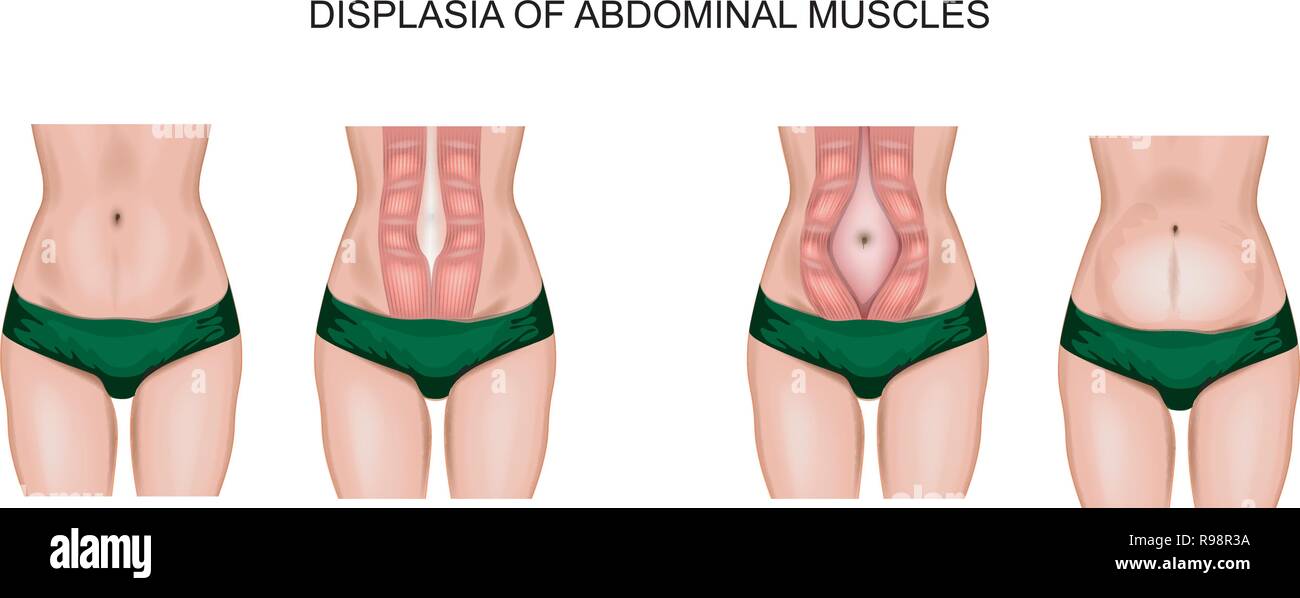

Illustration de diastasis des grands droits abdominaux après la grossesse Illustration de Vecteurhttps://www.alamyimages.fr/image-license-details/?v=1https://www.alamyimages.fr/illustration-de-diastasis-des-grands-droits-abdominaux-apres-la-grossesse-image229460430.html

Illustration de diastasis des grands droits abdominaux après la grossesse Illustration de Vecteurhttps://www.alamyimages.fr/image-license-details/?v=1https://www.alamyimages.fr/illustration-de-diastasis-des-grands-droits-abdominaux-apres-la-grossesse-image229460430.htmlRFR98R3A–Illustration de diastasis des grands droits abdominaux après la grossesse